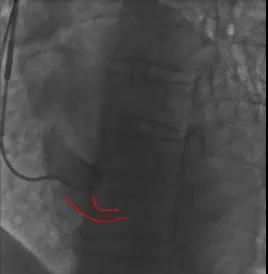

患者冠状窦开口异常,常规利用电生理十极寻找,无法进入cs,可以利用冒烟的方式确认开口位置,也可以利用患者之前的冠脉造影像来大概确认cs开口位置。

图三 冒烟寻找确认CS开口